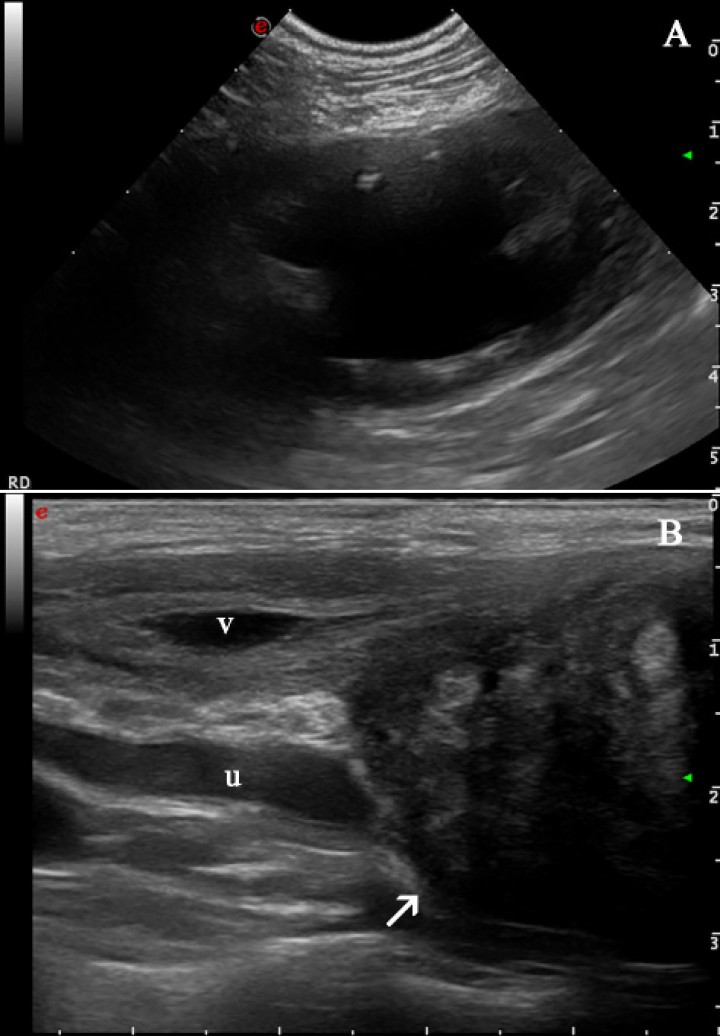

Tres meses más tarde la paciente regresó al hospital porque estaba apática y presentaba vómitos esporádicos. Se realizó una analítica sanguínea en la que se halló una insuficiencia renal marcada con unos valores de creatinina de 7,83 mg/dl (rango normal: 0,5 a 1,5 mg/dl) y urea de 147,7 mg/dl (rango normal: 20-50 mg/dl), y una anemia no regenerativa leve con un hematocrito del 35 % (rango normal: 37-55 %) y un RDW del 12 % (rango normal: 12,5-16,0 %). En el examen ecográfico del abdomen, se visualizó una masa caudal a la vejiga de características similares a la observada previamente, hidronefrosis severa del riñón derecho (Fig. 4A) e hidrouréter, que medía 1,61 cm de diámetro (Fig. 4B). Debido al mal pronóstico de la paciente los dueños decidieron realizar la eutanasia, no autorizando la realización de la necropsia.

<p>Imágenes ecográficas a los tres meses de la segunda presentación. (<strong>A</strong>) Hidronefrosis del riñón derecho: se observa una marcada dilatación de la pelvis renal y divertículos del riñón derecho por líquido anecogénico con una mínima remanencia de la corteza renal. (<strong>B</strong>) El uréter derecho (u) dorsal a la vejiga de la orina (v) e involucrado con la masa (flecha blanca) se visualiza dilatado (hidrouréter).</p>

Imágenes ecográficas a los tres meses de la segunda presentación. (A) Hidronefrosis del riñón derecho: se observa una marcada dilatación de la pelvis renal y divertículos del riñón derecho por líquido anecogénico con una mínima remanencia de la corteza renal. (B) El uréter derecho (u) dorsal a la vejiga de la orina (v) e involucrado con la masa (flecha blanca) se visualiza dilatado (hidrouréter).